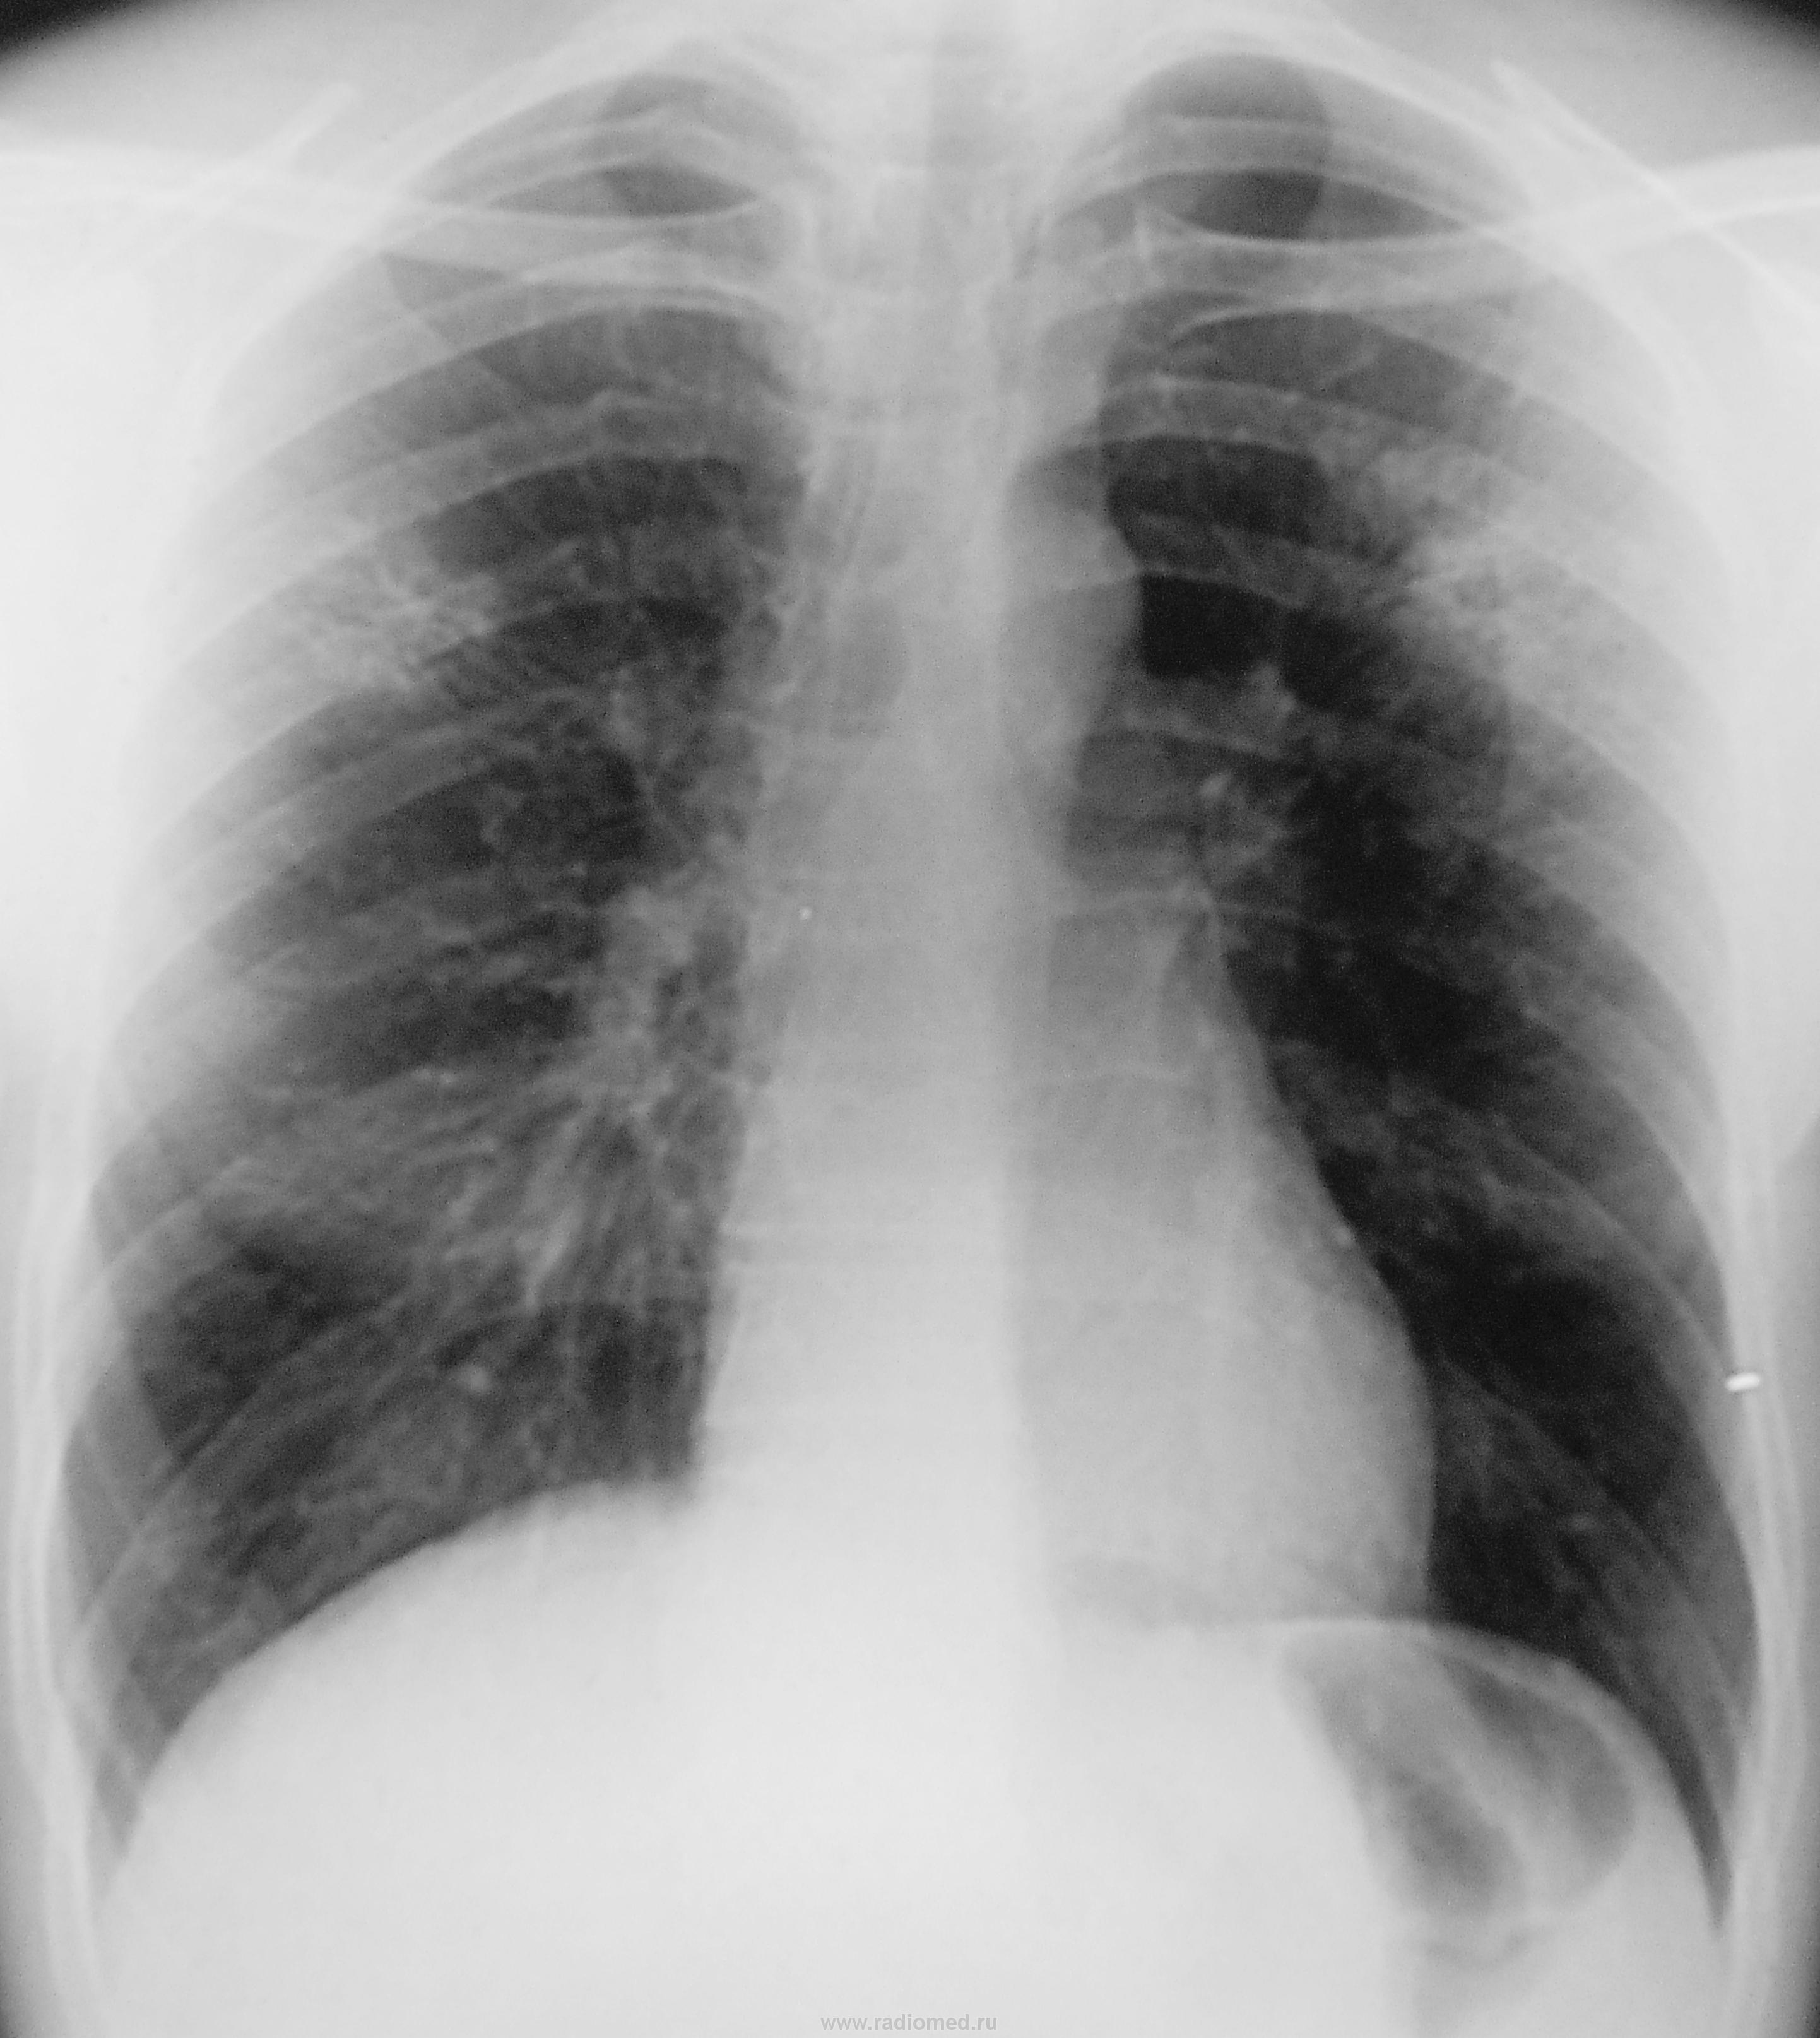

Но "поезд ушел", в облтубе пациент, там и КТ даже сделали (сегодня с зав. рентген-отделением облтуба общался), да и "палки" при микроскопии "улыбнулись".

И каков диагноз ПТД?

Вас интересует предварительный или уточненный после посева на среды?

Предварительный я озвучила,конечно,интересует точный диагноз.

Предварительный - инфильтративный, а более точный подождать надо, пока на средах рост будет.